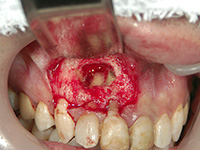

膿胞(のうほう)摘出

膿胞という袋状の病気ができていたため、手術によって摘出しました。

術後は歯ぐきの傷も治り、審美的にも改善しました。